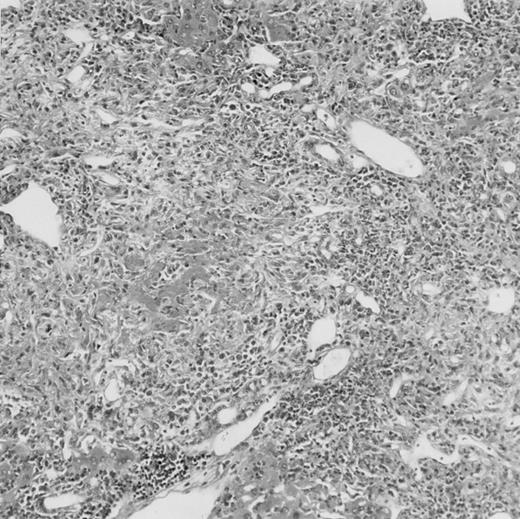

Histologic findings. Organs were collected at different times after BMT and tissue sections were stained with hematoxylin and eosin. Original magnifications for spleen (left) and liver (right) are ×40 and ×100, respectively. (A) B6 mice receiving FVB BM plus EpTK T cells. (B) Control group receiving BM only.

(C) B6 mice receiving FVB BM plus EpΔTK T cells and treated with GCV. (D) B6 mice receiving FVB BM plus EpΔTK T cells, treated with GCV, and developing a late onset GVHD (day 54).

FVB BM-grafted B6 mice: a model of lethal GVHD.We developed a model of GVHD resulting in 100% mortality soon after BMT using FVB mice, a strain not previously used as BM donors in experimental allogeneic BMT. We tested different combinations of recipient irradiation doses, as well as injected BM cell and CD3+ peripheral T-cell numbers. When 10-Gy–irradiated B6 mice were reconstituted with 107 FVB BM cells, we observed prolonged survival, whereas all ungrafted animals died before day 16 (Fig 2). In these conditions, more than 98% of splenocytes were of donor origin (Fig 3A). When 107 CD3+ peripheral T cells from mice of FVB genetic background were added to the FVB BMT, all animals died of GVHD between days 7 and 34 (Fig 2). Similar results were obtained using either PBS-treated mice receiving EpTK or EpΔTK peripheral T cells or GCV-treated mice receiving FVB nontransgenic peripheral T cells. Notably, this observation also indicates that both TK- and ΔTK-expressing T cells in the absence of GCV are fully competent to induce a lethal GVHD. Histopathologic examination of spleen and liver of these animals showed characteristic GVHD lesions such as (1) architecture disruption, necrosis, and congestion in the spleen; (2) hepatic periportal necrosis; (3) mononuclear portal infiltrates; and (4) endothelialitis of portal or centrolobular veinules (Fig 4A). By comparison, B6 mice receiving only FVB BM had a normal histology (Fig 4B).

Using this delivery mode, we observed that mice receiving a 7-day GCV treatment initiated at the time of transplantation were protected from GVHD. At day 60, the survival rate was 100% in the GCV-treated group receiving EpTK CD3+ T cells, and was still 92% at the end of a 120 day follow-up (Fig 2A). Protected mice were apparently healthy, presented no visible skin lesions, and gained weight comparably to controls receiving only BM (data not shown). Hematologic reconstitution was analyzed by flow cytometry at different times from day 14 to day 212. Splenocytes of GCV-treated animals were of donor H-2q origin in the B-cell (B220+) and non–B-cell (B220−) compartments, the latter containing donor Thy1.1+ T cells but no recipient Thy1.2+ T cells (Fig 3B). Finally, histological analysis in these animals showed nodular architecture in the spleen and no significant hepatocyte necrosis or portal mononuclear cell infiltrates in the liver (not shown) and similar to control animals receiving only BM. Taken together, these data indicate that a GCV treatment, administered at the onset of allogeneic BMT and with a course as short as 7 days, abrogates GVHD and allows a full recovery from the lethal irradiation.

Protection from GVHD was slightly less efficient in the group receiving EpΔTK CD3+ T cells. The survival rate was 79% at day 60 and 67% at day 120 (Fig 2B). However, two different outcomes must be distinguished. On the one hand, a majority of mice behaved as GCV-treated animals receiving EpTK T cells. They were apparently healthy, presented no skin lesions during a 120-day observation period, and showed complete donor-type hematologic reconstitution. There were no histological signs of GVHD in the spleen or liver (Fig 4C).

On the other hand, 5 of 19 mice exhibited signs suggesting the occurrence of a delayed GVHD (Table 1). Clinically, these animals presented weight loss and/or skin lesions on ears, neck, limbs, or abdomen, but only after day 40. In the absence of any further GCV treatment, 2 mice died 14 and 29 days after the occurrence of these signs (Table 1A) with histological signs of severe GVHD (Fig 4D). These results suggest that, in these mice, the 7-day GCV treatment was sufficient to prevent early, but not delayed GVHD.